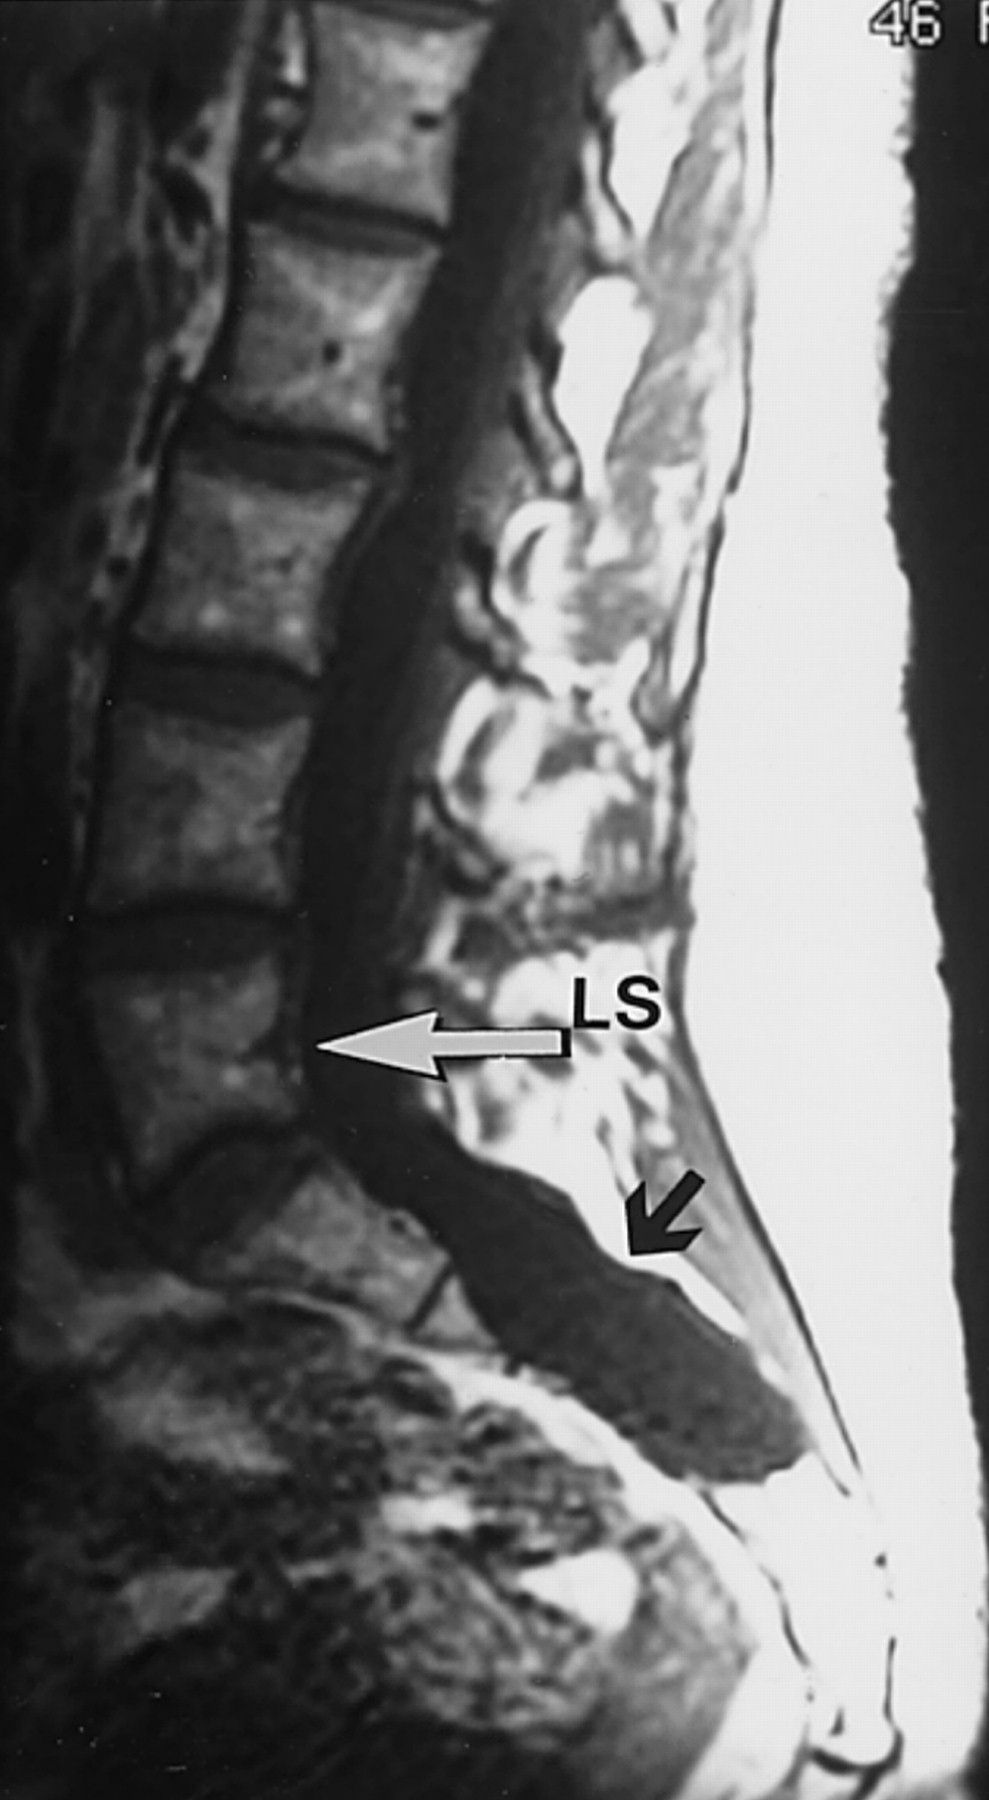

Neonatalnaya forma sindroma marfana klinicheskoe opisanie i kompleksnyj podhod k diagnostike i lecheniyu tema nauchnoj stati po klinicheskoj medicine chitajte besplatno tekst nauchno issledovatelskoj raboty v elektronnoj biblioteke kiberleninka (Тип файлу jpg)

Neonatalnaya Forma Sindroma Marfana Klinicheskoe Opisanie I Kompleksnyj Podhod K Diagnostike I Lecheniyu Tema Nauchnoj Stati Po Klinicheskoj Medicine Chitajte Besplatno Tekst Nauchno Issledovatelskoj Raboty V Elektronnoj Biblioteke Kiberleninka